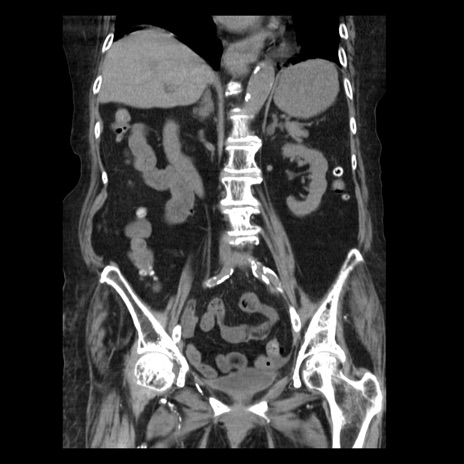

症例14(冠状断像)

【症例】 90歳代女性

【主訴】 腹痛・嘔吐

【現病歴】今朝から左側腹部痛を認めた。 経過観察していたが、嘔吐を認めたため来院。

【既往歴】 子宮癌術後

【身体所見】 意識清明、BP 127/54mmHg、P 98bpm Sp02 95%(RA)、BT 35.8°C、腹部平坦・軟腸ぜん動音聴取良好、右下腹部圧痛(+) 反跳痛なし

【データ】WBC 9800、CRP 0.46